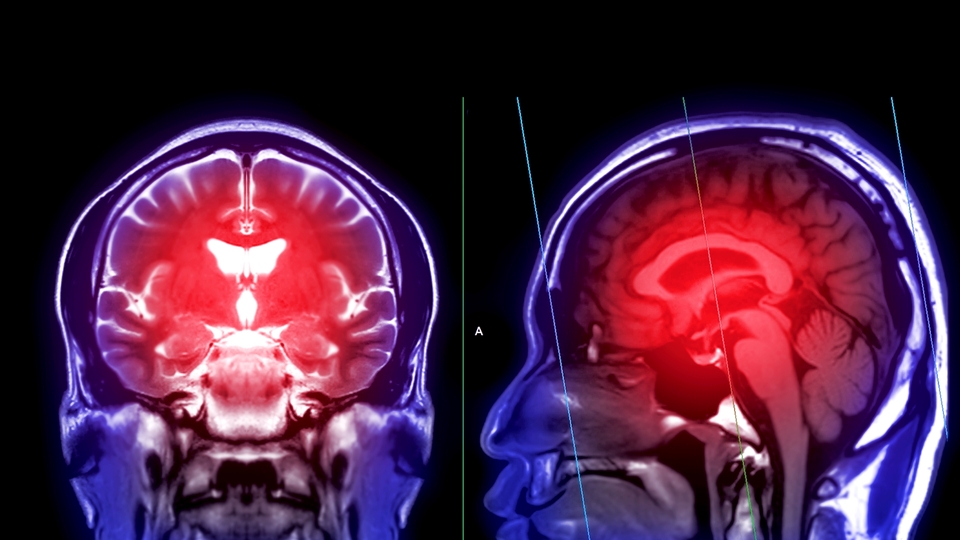

Günümüzde kalp ve damar hastalıkları nedeniyle pıhtı oluşması, emboli atması özellikle de inme (felç), dünyada ölüm nedenleri arasında ilk sıralarda yer alıyor. Bu ciddi tablonun en önemli nedenlerinden birinin şah damarı daralması yani tıptaki adıyla karotis arter stenozu olduğunu belirten Kalp ve Damar Cerrahisi Uzmanı Doç. Dr. Macit Bitargil, "Şah damarı, boynun her iki yanında yer alan ve kalpten çıkıp direkt olarak beyine kan taşıyan ana damarlardır. Bu damarlarda zamanla kolesterol yüksekliği, tansiyon yüksekliği, sigara kullanımı, şeker hastalığı ve yaşlanma gibi nedenlerle plaklar oluşabilir" dedi.

Doç. Dr. Bitargil, bu plakların damarı daraltarak beyne giden kan akış paternini bozduğunu kaydederek şunları söyledi: "Oluşan türbülan akım ve damardaki darlık sonucu sistem pıhtı üretebilir. Embolinin beyne ulaşması ve beyindeki ilgili merkezi etkilemesi sonucu geçici iskemik ataklar (TIA) veya kalıcı inme (felç) tablosu gelişebilir."